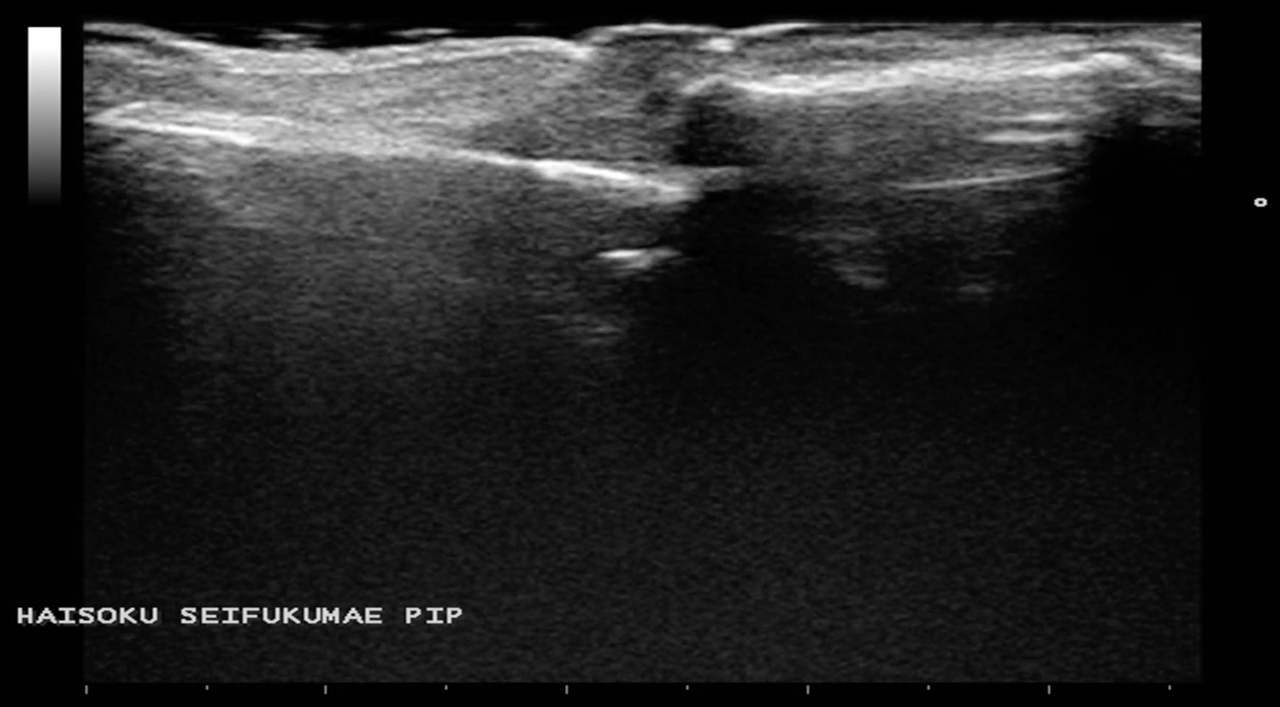

小指PIP関節脱臼骨折(突き指の重症例)

スワンネック変形(整復前)

整復の前後の確認を念の為エコーでも行いました。すると、掌側板の裂離骨折を疑うような所見を確認しました。

提携先の整形外科へ受診していただくと、やはり骨折を併発しているとのご返答をいただきました。脱臼に伴い中節骨の骨折を起こしていたようです。